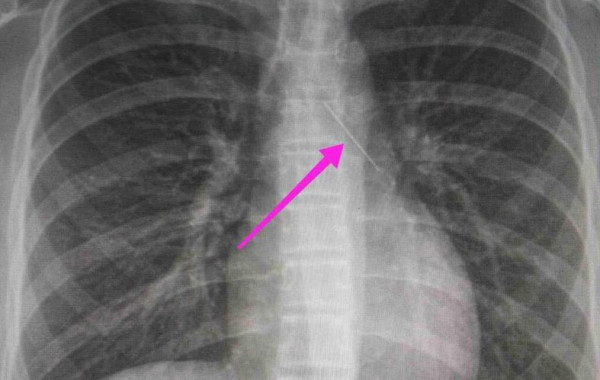

Οι γιατροί κατάφεραν να αφαιρέσουν την καρφίτσα από τα πνευμόνια του κοριτσιού

Τι είπε ο καθηγητής Πνευμονολογίας, Θεόδωρος Βασιλακόπουλος